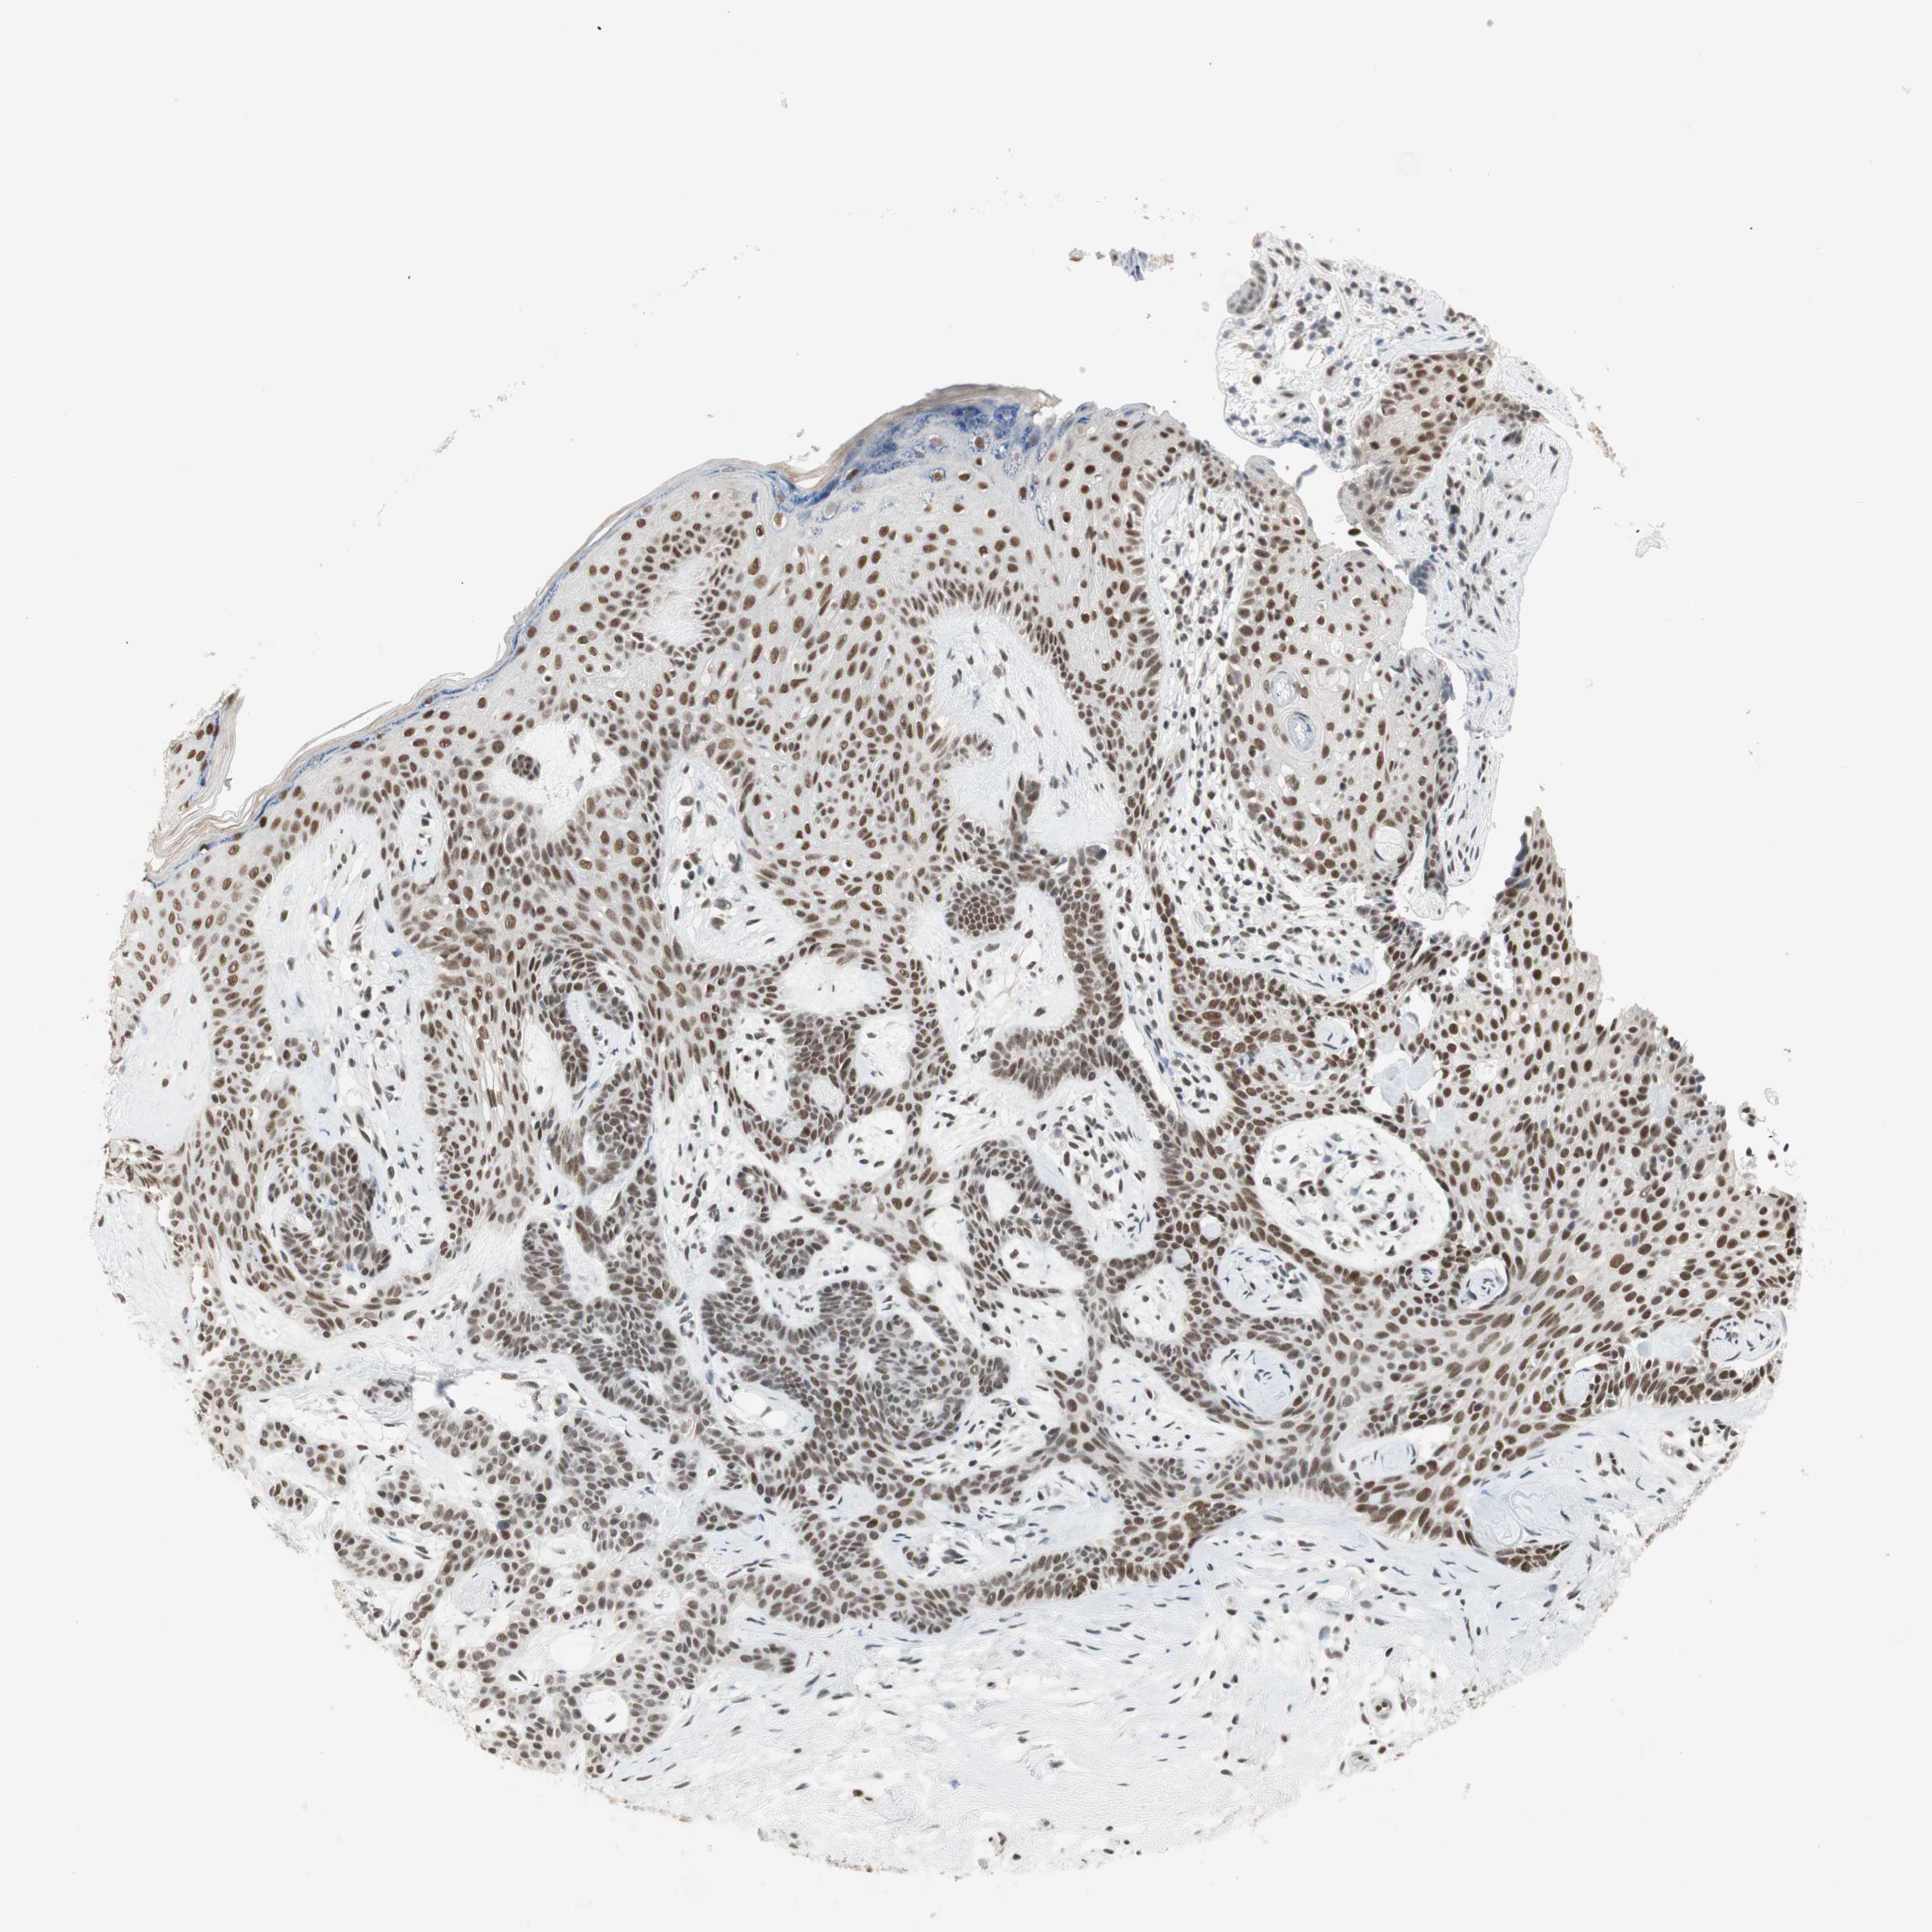

SKIN CANCER - Protein expressioni

A mouse-over function shows sample information and annotation data. Click on an image to view it in a full screen mode. Samples can be filtered based on level of antibody staining by selecting one or several of the following categories: high, medium, low and not detected. The assay and annotation is described here.

Antibody stainingi

Antibody staining in the annotated cell types in the current human tissue is reported as not detected, low, medium, or high, based on conventional immunohistochemistry profiling in selected tissues. This score is based on the combination of the staining intensity and fraction of stained cells.

Each image is clickable and will lead to virtual microscopy that enables deeper exploration of all samples and also displays staining intensity scores, fraction scores and subcellular localization as well as patient and tissue information for each sample.

Antibody HPA006714

Antibody CAB079946

Antibody CAB079947

Staining

High

Medium

Low

Not detected

Intensity

Strong

Moderate

Weak

Negative

Quantity

>75%

75%-25%

<25%

None

Location

Nuclear

Cytoplasmic/membranous

Cytoplasmic/membranous,nuclear

Squamous cell carcinoma, NOS

Squamous cell carcinoma, metastatic, NOS

Basal cell carcinoma

Papilloma, NOS